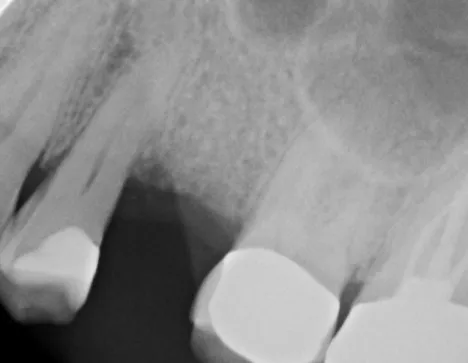

Dr.-Geivelis_Fig.1

Fig. 1. X-ray image of tooth to be restored prior to root extraction.